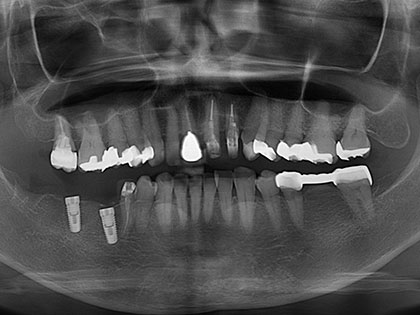

• 治療完了時の写真がこちら

• インプラント治療完了時1

• 治療の詳細

• 症例

• 60歳女性

• 左下6番目、7番目 インプラント